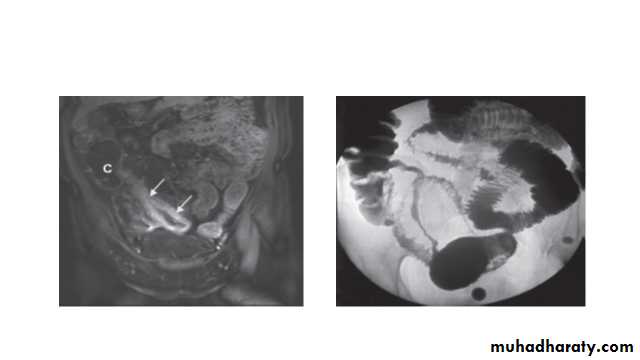

All children and most adults with Crohn’s disease should have upper gastrointestinal endoscopyInvestigations: Radiology

Barium enema is a less sensitive investigation than colonoscopy in patients with colitis and, where colonoscopy is incomplete, a CT colonogram is preferred.Small bowel imaging is essential to complete staging of Crohn’s disease. Traditional contrast imaging by barium follow-through demonstrates affected areas of the bowel as narrowed and ulcerated, often with multiple strictures. This has now largely been replaced by MRI enterography, which is a sensitive way of detecting extra intestinal manifestations and of assessing pelvic and perineal involvement.